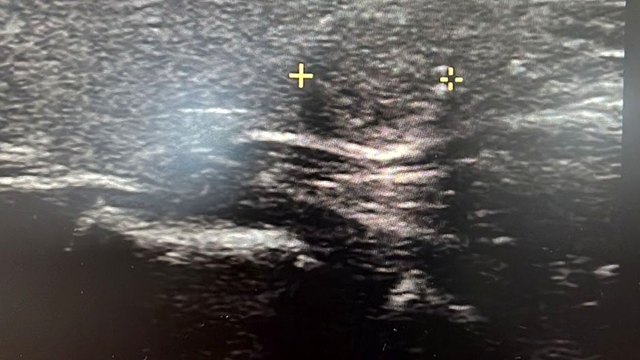

Tiroit nodülü tespitinde farkındalığın artığını ifade eden Dr. Demir, "Nodül tespitindeki farkındalığımız arttı. Tiroit ultrasonu kullanıyor olmamız da bu artışa etken oldu. 'Bası bulgusu' ile dokunarak muayene ettiğimizde; mevcut olan nodüllerin yaklaşık yüzde 20’sini tespit edebiliyoruz. Nodüllerin birçoğunun özelliklerini ve boyutlarını ise tiroit ultrasonu ile tespit ediyoruz. Son dönemlerde vakalarda artış var. Bazen hiçbir semptomu olmayan hastalarda da tiroit nodülleri tespit ediyoruz. Nodülleri özelliklerine göre değerlendirerek gerekli hastalardan biyopsi alıyoruz. İyi ya kötü huylu nodüle göre tedavi uyguluyoruz. Nodülü belli aralıklarla takip ediyoruz. Tiroit nodüllerinin yüzde 10 ila 20 kadarı kötü huylu olabiliyor. Birçok kanser türü erkek hastalarda fazla görülürken, özellikle tiroit kanseri sıklığı kadın hastalarımızda daha yüksektir. Kadın hastalar daha sık muayeneye geliyor ve farkındalıkları daha yüksek" diye konuştu.